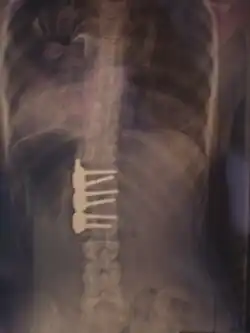

![]() Рентгеновский снимок позвоночника пациента со сколиозом с левосторонним искривлением в поясничном отделе и правосторонним искривлением в грудном отделе позвоночника. | |

Величина искривления позвоночника измеряется с помощью рентгеновского снимка всего позвоночника стоя. Возможны и врождённые рёберные деформации и деформации тел позвонков. С помощью этой информации можно отличить идиопатический и врождённый сколиоз. На рентгеновском снимке в боковой проекции можно также определить, есть ли врождённые деформации в этой плоскости или нарушения нормальных изгибов позвоночника — физиологических кифозов и лордозов.

Схема анализа рентгеновского снимка для определения угла искривления разработана в 50-х годах XX века американским ортопедом Дж. Коббом (англ. John Robert Cobb). Угол искривления, измеренный по рентгеновским снимкам теперь называется «углом по Коббу». Для определения угла деформации на передне-задней рентгенограмме проводят две линии, параллельных замыкательным пластинкам нейтральных позвонков. В точке пересечения этих линий или перпендикуляров к ним измеряют угол сколиоза.